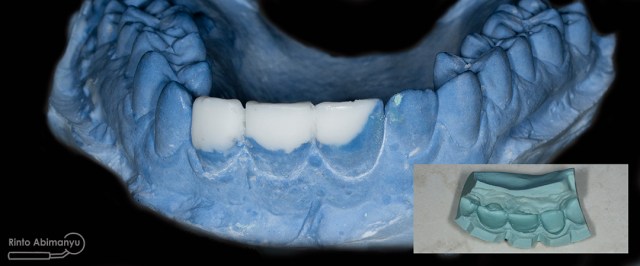

Wax up ini merupakan proses yang penting bila kita berhadapan dengan kasus yang kondisi giginya tidak utuh, dari sanalah nanti kita mendapatkan visualisasi perkiraan hasil akhir perawatan… Wax up bisa dilakukan sendiri bila kita mempunyai alat dan bahan yang diperlukan atau bisa dikirimkan ke lab… Tapi saya mempunyai istri yang juga seorang prostodontis jadi saya minta tolong dia untuk melakukan wax up hehehe :p

Hasil wax up dan pada insert terlihat hasil cetak untuk silicone index

Model yang sudah diwax up kemudian saya cetak dengan putty double impression yang nanti cetakan tersebut dijadikan sebagai silicone index pembuatan mahkota sementara…